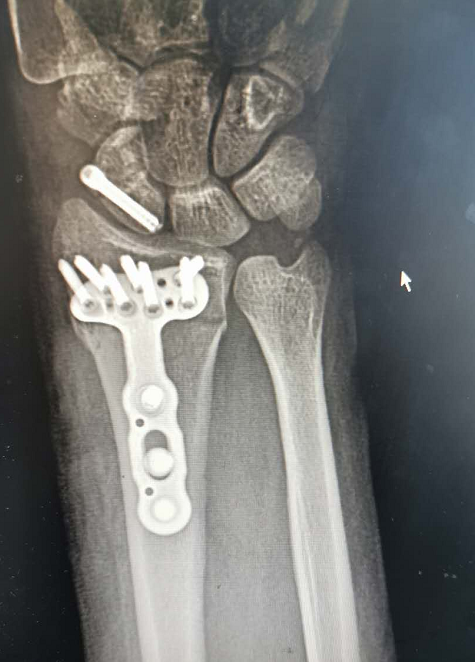

据骨科吴主任介绍

经过检查发现

小李的左桡骨远端粉碎性骨折

左腕舟骨骨折、腰椎骨折

随后,吴主任为小李进行了

左桡骨远端粉碎性骨折

左腕舟骨骨折切开复位内固定手术